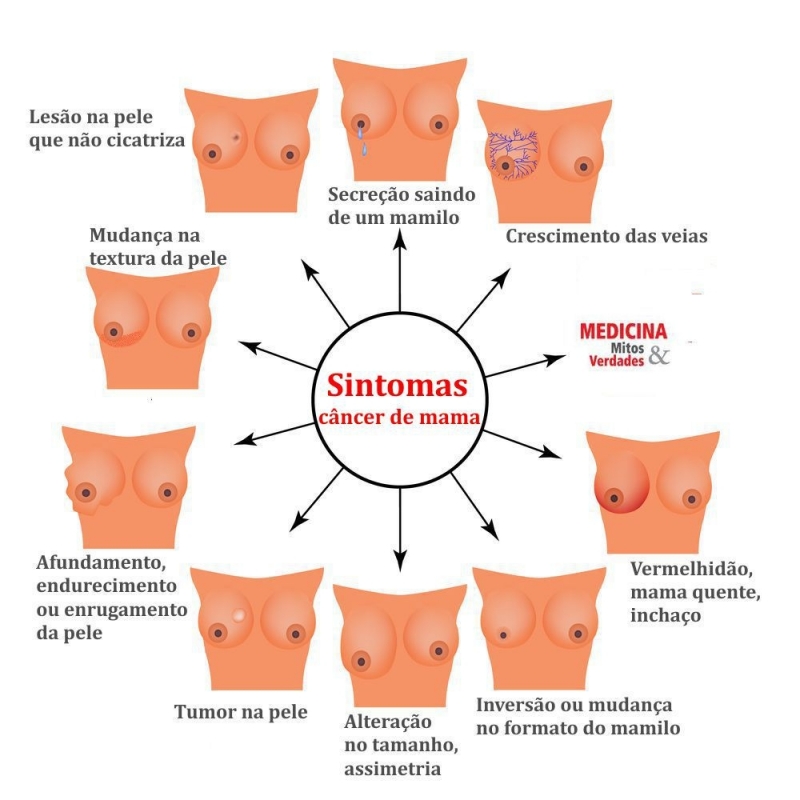

médicos responsável pela mama Santa Cecília tem a capacidade de auxiliar pacientes com câncer de mama ou prevenir o surgimento da doença. Como apenas o autoexame não é suficiente para perceber a presença de doenças o papel do profissional é garantir a prevenção, diagnóstico, tratamento e reabilitação dos pacientes. Sendo assim, é possível garantir qualidade de vida e bem-estar às mulheres.